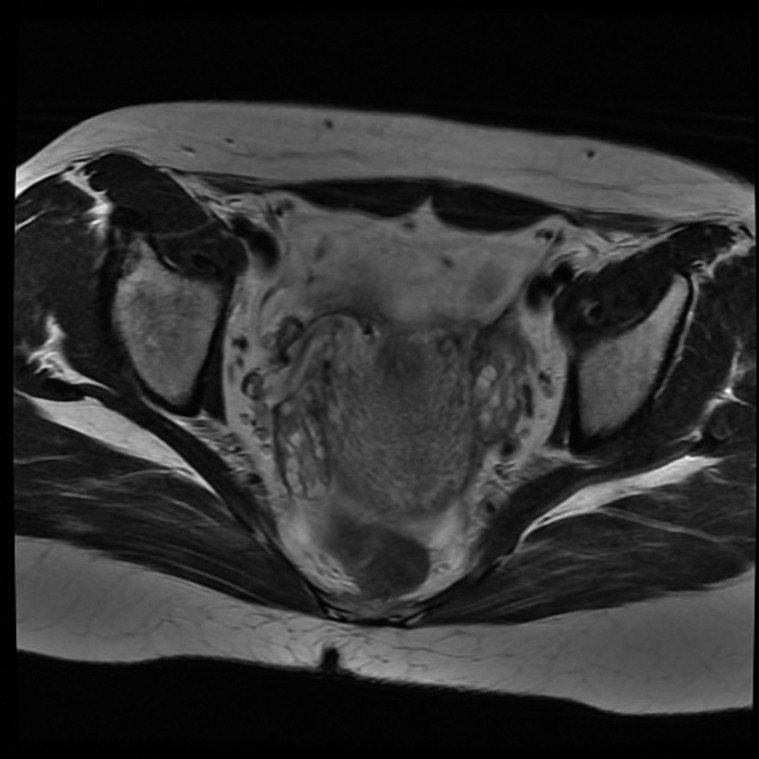

Case presentation: A 26-year-old woman presented in the later part of her pregnancy with widespread hirsutism. Biochemical testing confirmed hyperandrogenism (testosterone, 13.7 nmol/l and second-trimester pregnancy range, 0.9-4.9 nmol/l), although she had no history of menstrual disturbance, hirsutism or acne prior to conception. Radiological evaluation (ultrasound and magnetic resonance imaging) revealed multiple cystic lesions in both ovaries, leading to a presumptive diagnosis of hyperreactio luteinalis (HL). The implications of maternal hyperandrogenism on foetal virilisation were considered and the patient was counselled appropriately. She delivered a healthy baby boy uneventfully. Androgen levels, hirsutism and acne normalised within a few weeks of delivery.